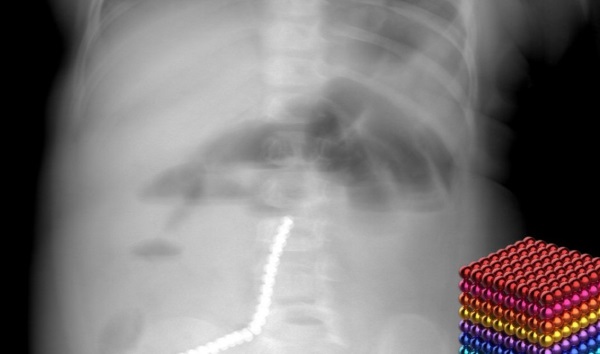

В Бурятии ребёнок проглотил 20 магнитных шариков

Ему пришлось удалить часть кишечника

В детской республиканской клинической больнице (ДРКБ) спасли двухлетнего жителя Бурятии, который проглотил 20 магнитных шариков от так называемого неокуба. Это привело к экстренному хирургическому вмешательству.

Всё произошло в начале февраля. Малыш поступил в приёмно-диагностическое отделение ДРКБ с рвотой. Рентгенография сразу показала причину – множество инородных тел в пищеварительном тракте.

Врачам удалось удалить 9 магнитов эндоскопически (ФГДС). Однако остальные мигрировали по кишечнику, вызвав его перфорацию.

- Петли тонкой, сигмовидной и слепой кишки слиплись между собой из-за магнитного притяжения, — пояснил хирург-эндоскопист ДРКБ Булат Шагдаров.

Потребовался переход к открытой операции. Медики выполнили лапаротомию и уже в процессе обнаружили и устранили тяжелейшие последствия. Они ушили образовавшиеся межкишечные свищи и удалили участок тонкой кишки с перфорацией размером до двух сантиметров.

Отдельная опасность заключалась в том, что часть магнитов опустилась в аппендикс, который также пришлось вырезать. Маленького пациента сначала поместили в отделение анестезиологии и реанимации. Сейчас он долечивается в профильном отделении.